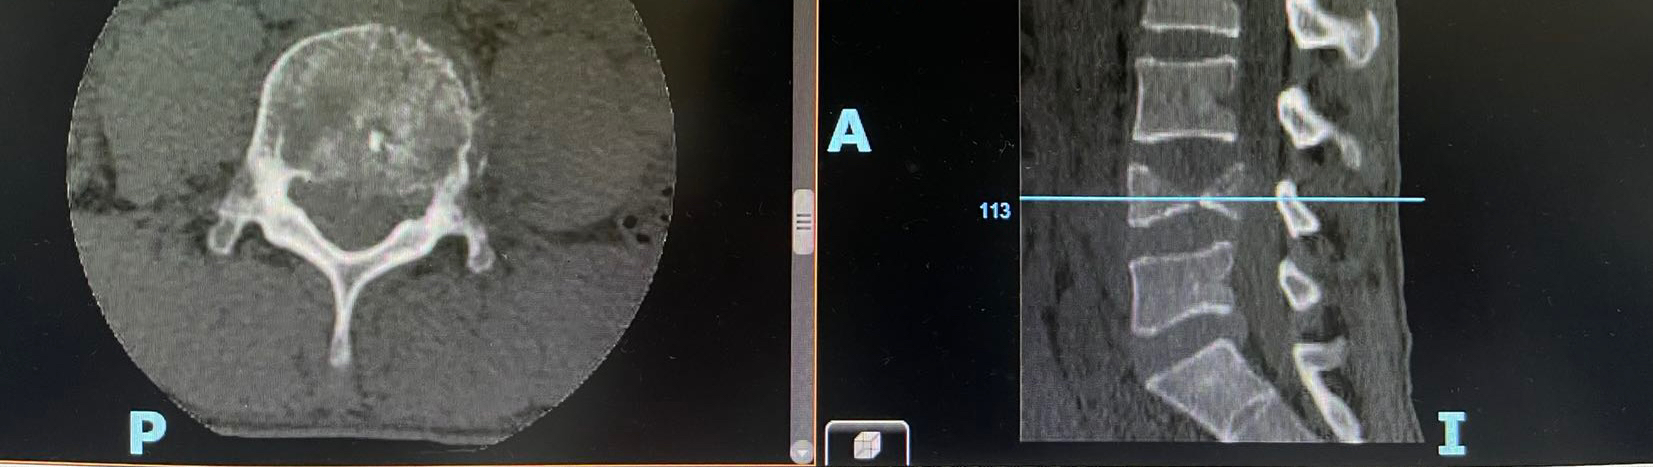

患者中年男性,消化道恶性肿瘤术后5年,胸腰椎转移。患者就诊主要症状:胸腰背部疼痛、腰骶交界区为重,夜间明显,弯腰受限,双侧小腿外侧麻木;体查:T10-11、L4-S1节段压痛、叩痛阳性,疼痛可放射至右侧小腿及足背,双侧L5以下感觉平面减退,右侧小腿及踝关节拮抗肌肌力IV级,余未及异常。

影像学检查如下: